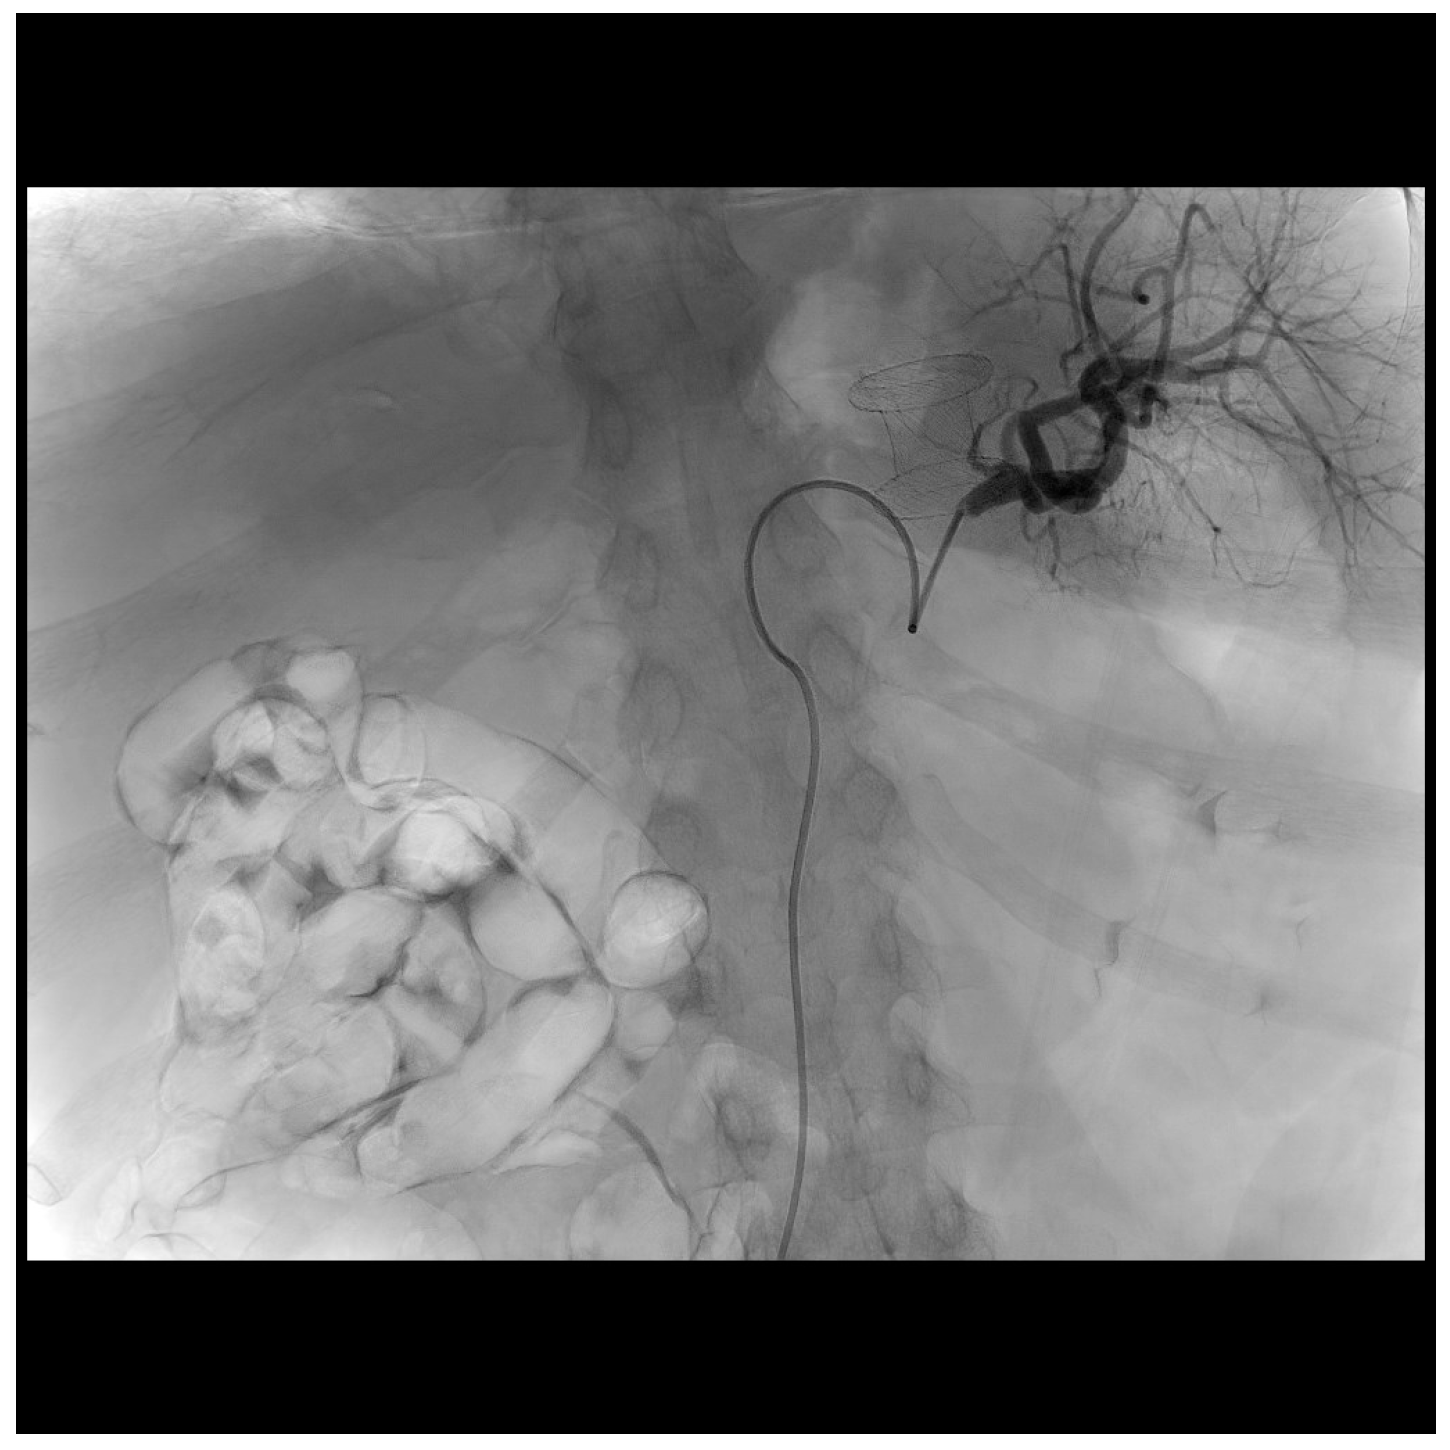

2. Case Presentation